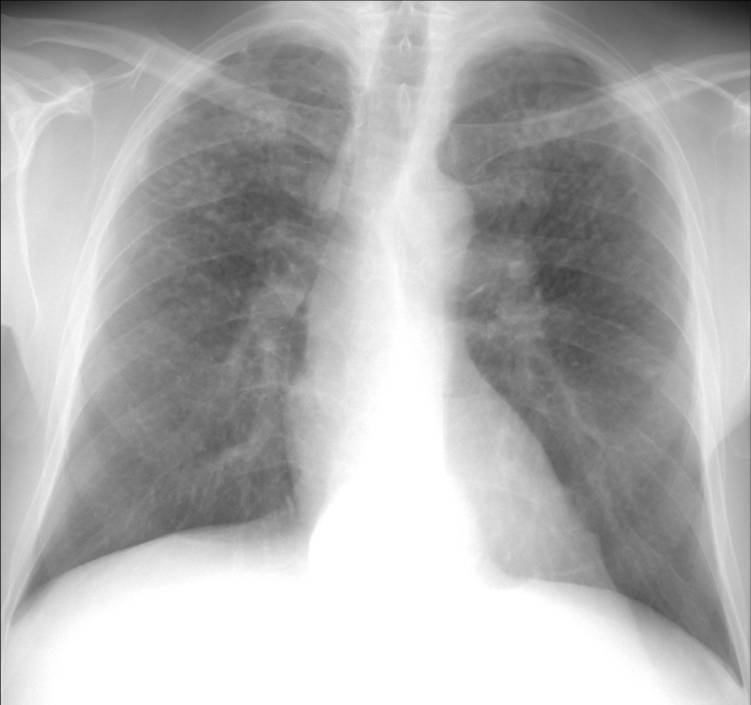

His current chest x-ray and high resolution CT scan are shown in figures 1a and 1b respectively.

Figure 1a: Chest radiograph demonstrating upper lobe predominant nodular infiltrates, hilar adenopathy, and some apical pleura reaction

Of the metals listed, only beryllium could cause both this clinical picture and radiographic appearance with these exposures. Beryllium copper alloys are used in many high technologic and electronics applications including computers. Recycling computers to reclaim copper or other metals can lead to beryllium exposure in metal recycling workers(1). Chronic beryllium disease (CBD) is a granulomatous disease with slowly progressive respiratory symptoms caused by exposure and subsequent sensitization to beryllium. The typical HRCT appearance is similar to sarcoidosis and features primarily diffuse pulmonary nodules in a peribronchovascular and/or perilymphatic distribution. The pulmonary function abnormalities include obstruction, restriction, and mixed patterns (2, 3). In this case, the patient's cigarette abuse could have contributed to his obstruction but the lack of any emphysema on the CT scan makes that unlikely to be the sole explanation. Thus, this patient had potential for beryllium exposure during his work in metal recycling and has a disease course, radiographic, and physiologic presentation consistent with chronic beryllium disease.